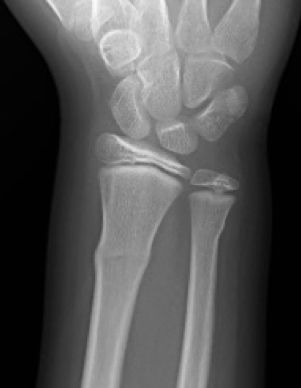

C. Fracturas en tallo verde

Las fracturas de tallo verde, cuando permanece una parte del periostio intacta y la otra cortical está desplazada, son diferentes de las fracturas en rodete, en las que existe un típico “abombamiento” del hueso metafisario (Figura 13).

Figura 13: a, b, Radiografía antero-posterior y lateral donde se aprecia un “abombamiento” de la región metafisaria distal del radio compatible con fractura en rodete.